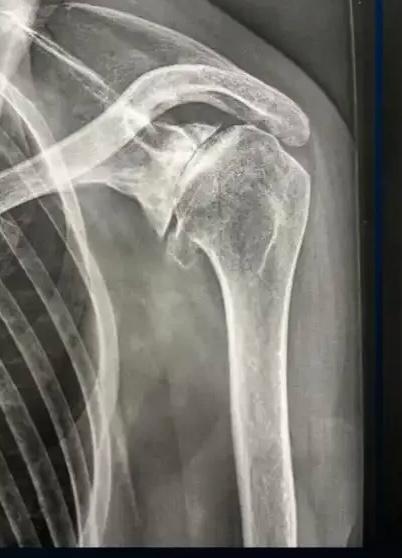

Radiographie d'une arthrose de l'épaule excentrée

Radiographie : Arthrose excentrée de l'épaule

La radiographie standard : face, profil, rotation interne/externe

Elle va apporter une grande partie des informations nécessaires pour évaluer l'arthrose de l'épaule :

• Pincement de l'interligne articulaire (entre la tête humérale et la glène de l'omoplate)

• Condensation de l'os sous-chondral

• Ostéophytes (inférieur, antérieur, postérieur…) - intérêt +++ des clichés en rotation interne/externe

• Forme de la tête humérale (aplatissement, perte de sphéricité…)

• Géodes, lacunes intra-osseuses

• Centrage de la tête humérale (l'excentration avec surélévation serait en faveur d'une lésion associée de la coiffe des rotateurs)

• Évaluation du stock osseux (surtout sur la glène de l'omoplate)